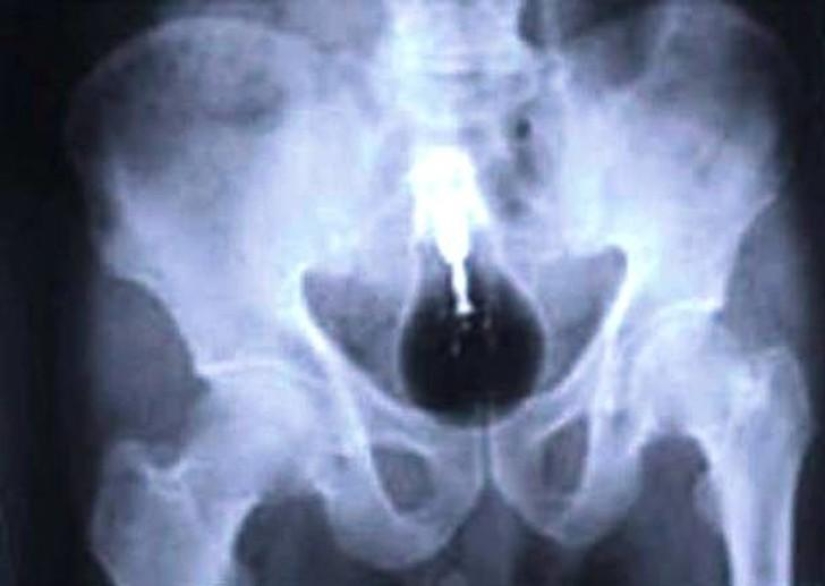

Mobile phone.